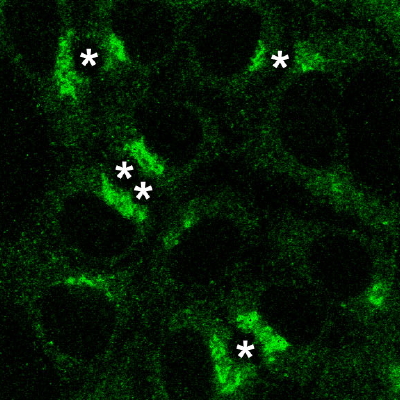

Figure 1 : Images par contraste de phase d’un épithélium de cellules WIF-B9 et par immunofluorescence de la protéine ATP7B excrétant le cuivre vers la bile dans ces cellules.

Ajout de 1 µM de CuSO4 au milieu de culture pendant 2 heures, puis de 10 µM de P3 pendant 3 heures. La protéine est à nouveau entre les noyaux et le canalicule. Le cuivre est donc retourné à son état basal grâce à P3.